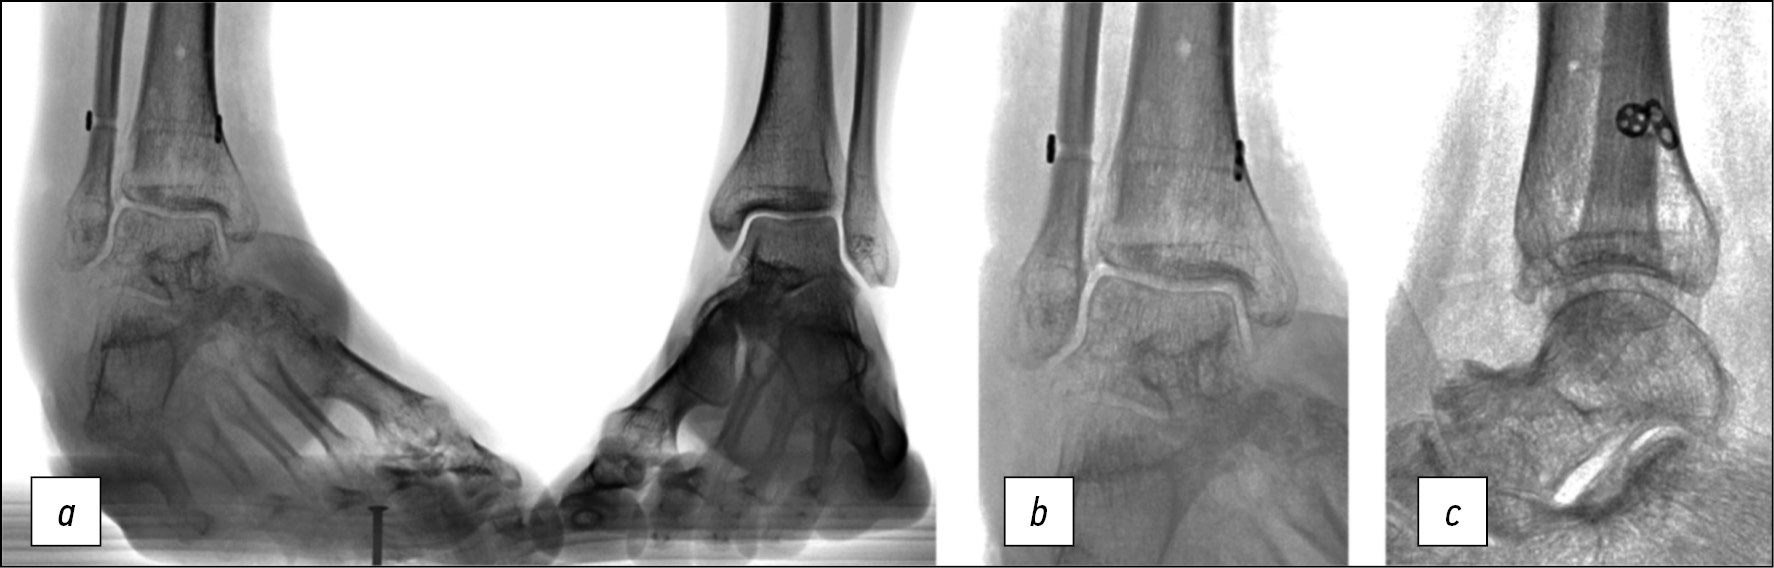

Пациент К., женского пола, 34 года, 328 дней с момента травмы — надсиндесмозного перелома дистальной трети диафиза левой малоберцовой кости, подвывиха стопы кнаружи. Спустя 6 дней после получения травмы выполнено оперативное вмешательство в объёме открытой репозиции и накостного остеосинтеза малоберцовой кости, фиксации дистального межберцового синдесмоза позиционным винтом. На контрольных рентгенограммах диагностирован сохраняющийся наружный подвывих стопы, в связи с чем через 1 месяц после первой операции выполнено повторное вмешательство — перепроведение позиционного винта. Контрольные рентгенограммы после повторного вмешательства демонстрировали сохраняющийся наружный подвывих стопы (рис. 4а). Через 8 недель после повторного вмешательства выполнено удаление позиционного винта. У пациентки сохранялись жалобы, связанные с нестабильностью голеностопного сустава.

Рис. 4. Рентгенограммы пациентки К. после предшествующих оперативных вмешательств: a, b — расширение медиальной щели голеностопного сустава, c — расширение межберцового пространства, d — рентгенограмма в боковой проекции

Fig. 4. X-rays of patient K. after previous surgery: a, b — increased medial clear space, c — increased tibiofibular space, d — lateral X-ray

Рентгенограммы через 6 месяцев после удаления позиционного винта демонстрируют расширение медиальной щели голеностопного сустава (рис. 4b), межберцового пространства (рис. 4c, d).

Послеоперационные рентгенограммы в прямой (рис. 5a) и боковой (рис. 5b) проекциях демонстрируют восстановление взаимоотношений в голеностопном суставе. На рентгенограммах в боковой проекции (рис. 5c, d) наблюдается ограниченный шарнирными устройствами объём активных движений: подошвенное сгибание (рис. 5c) ограничено 5°. На гониограммах (рис. 5e, f) и подограммах (рис. 5g, h) на 7-е сутки после операции — ходьба без дополнительных средств опоры в условиях внешней фиксации, демонстрирующая наличие сниженного активного тыльного сгибания стопы, умеренной асимметрии при равномерном распределении нагрузки на передний и задний отделы стопы оперированной конечности. Период госпитализации — 14 суток, срок фиксации в аппарате Илизарова — 37 суток.

Рис. 5. a — послеоперационная рентгенограмма пациентки К. в прямой проекции, b — послеоперационная рентгенограмма в боковой проекции, c, d — рентгенограмма в боковой проекции: ограниченный шарнирными устройствами объём активных движений, e, f — гониограммы, g, h — подограммы

Fig. 5. Postoperative X-rays of patient K.: a — A-P-view, b — lateral view, c, d — lateral X-rays demonstrating limited by hinges range of motion, e, f — gait analysis, g, h — computer podography

Рентгенограммы голеностопного сустава в прямой проекции с внутренней ротацией (стоя с нагрузкой) (рис. 6a) и в боковой проекции (рис. 6b) демонстрируют восстановление взаимоотношений в голеностопном суставе.

Рис. 6. Рентгенограммы пациентки К. после демонтажа аппарата Илизарова: a — в прямой проекции с внутренней ротацией, b — в боковой проекции

Fig. 6. X-rays of patient K. after Ilizarov fixator removal: a — mortise view, b — lateral view